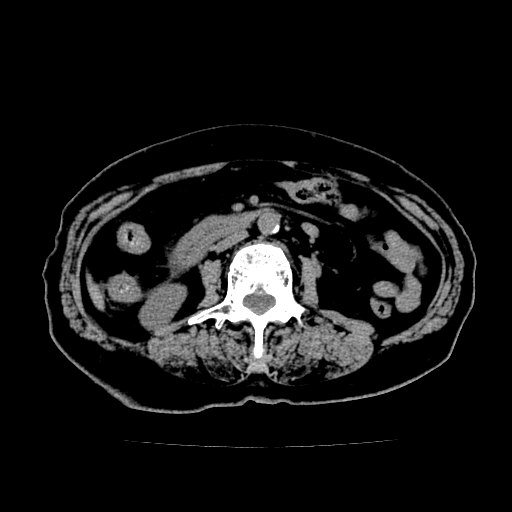

以下是引用zsl6918在2009-2-7 22:12:00的发言:[br]结合临床支持胰腺炎,建议强化查明胆总管扩张的原因。